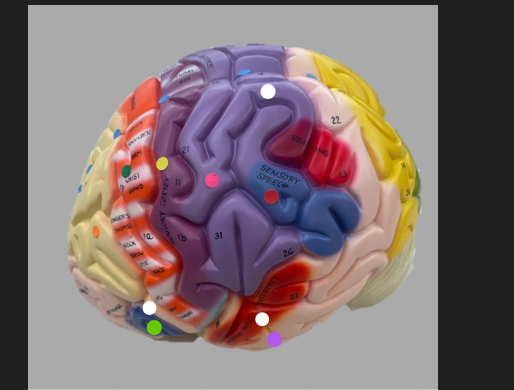

orange dot

frontal lobe

blue dot

longitudinal fissure

dark green dot

precentral gyrus

pink dot

postcentral gyrus

yellow dot

central sulcus

white dot

parietal lobe

light green dot

Broca’s Area

red dot

Wernicke’s Area

orange dot

occipital lobe

blue dot

parieto-occipital sulcus